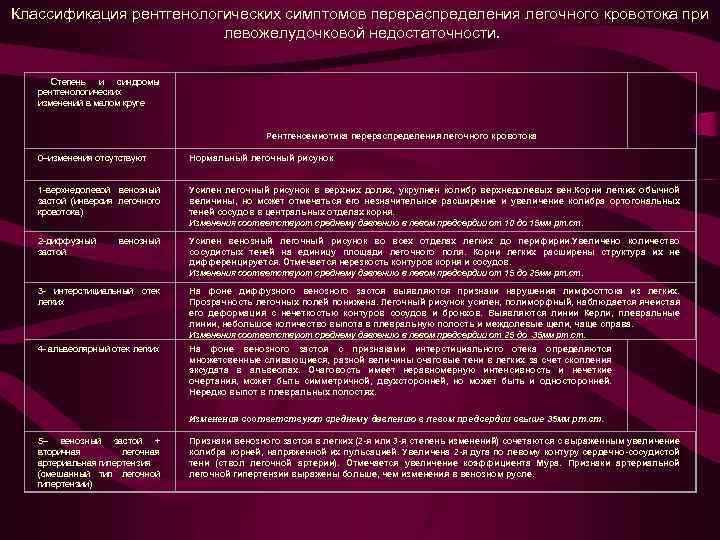

Рентгеносемиотика левожелудочковой недостаточности Рентгенологические симптомы перераспределения легочного кровотока - это проявления функциональной несостоятельности левого желудочка В практическом пользовании удобна классификация, отражающая единый подход к патофизиологическому развитию и клинической значимости дисфункции миокарда

Рентгеносемиотика левожелудочковой недостаточности Рентгенологические симптомы перераспределения легочного кровотока - это проявления функциональной несостоятельности левого желудочка В практическом пользовании удобна классификация, отражающая единый подход к патофизиологическому развитию и клинической значимости дисфункции миокарда

Классификация рентгенологических симптомов перераспределения легочного кровотока при левожелудочковой недостаточности. Степень и синдромы рентгенологических изменений в малом круге Рентгенсемиотика перераспределения легочного кровотока 0–изменения отсутствуют Нормальный легочный рисунок 1 -верхнедолевой венозный застой (инверсия легочного кровотока) Усилен легочный рисунок в верхних долях, укрупнен колибр верхнедолевых вен. Корни легких обычной величины, но может отмечаться его незначительное расширение и увеличение колибра ортогональных теней сосудов в центральных отделах корня. Изменения соответствуют среднему давлению в левом предсердии от 10 до 15 мм рт. ст. 2 -диффузный застой венозный Усилен венозный легочный рисунок во всех отделах легких до перифирии. Увеличено количество сосудистых теней на единицу площади легочного поля. Корни легких расширены структура их не дифференцируется. Отмечается нерезкость контуров корня и сосудов. Изменения соответствуют среднему давлению в левом предсердии от 15 до 25 мм рт. ст. 3 - интерстициальный отек легких На фоне диффузного венозного застоя выявляются признаки нарушения лимфооттока из легких. Прозрачность легочных полей понижена. Легочный рисунок усилен, полиморфный, наблюдается ячеистая его деформация с нечеткостью контуров сосудов и бронхов. Выявляются линии Керли, плевральные линии, небольшое количество выпота в плевральную полость и междолевые щели, чаще справа. Изменения соответствуют среднему давлению в левом предсердии от 25 до 35 мм рт. ст. 4 - альвеолярный отек легких На фоне венозного застоя с признаками интерстициального отека определяются множетсвенные сливающиеся, разной величины очаговые тени в легких за счет скопления эксудата в альвеолах. Очаговость имеет неравномерную интенсивность и нечеткие очертания, может быть симметричной, двухсторонней, но может быть и односторонней. Нередко выпот в плевральных полостях. Изменения соответствуют среднему давлению в левом предсердии свыше 35 мм рт. ст. 5– венозный застой + вторичная легочная артериальная гипертензия (смешанный тип легочной гипертензии) Признаки венозного застоя в легких (2 -я или 3 -я степень изменений) сочетаются с выраженным увеличение колибра корней, напряженной их пульсацией. Увеличена 2 -я дуга по левому контуру сердечно-сосудистой тени (ствол легочной артерии). Отмечается увеличение коэффициента Мура. Признаки артериальной легочной гипертензии выражены больше, чем изменения в венозном русле.

Классификация рентгенологических симптомов перераспределения легочного кровотока при левожелудочковой недостаточности. Степень и синдромы рентгенологических изменений в малом круге Рентгенсемиотика перераспределения легочного кровотока 0–изменения отсутствуют Нормальный легочный рисунок 1 -верхнедолевой венозный застой (инверсия легочного кровотока) Усилен легочный рисунок в верхних долях, укрупнен колибр верхнедолевых вен. Корни легких обычной величины, но может отмечаться его незначительное расширение и увеличение колибра ортогональных теней сосудов в центральных отделах корня. Изменения соответствуют среднему давлению в левом предсердии от 10 до 15 мм рт. ст. 2 -диффузный застой венозный Усилен венозный легочный рисунок во всех отделах легких до перифирии. Увеличено количество сосудистых теней на единицу площади легочного поля. Корни легких расширены структура их не дифференцируется. Отмечается нерезкость контуров корня и сосудов. Изменения соответствуют среднему давлению в левом предсердии от 15 до 25 мм рт. ст. 3 - интерстициальный отек легких На фоне диффузного венозного застоя выявляются признаки нарушения лимфооттока из легких. Прозрачность легочных полей понижена. Легочный рисунок усилен, полиморфный, наблюдается ячеистая его деформация с нечеткостью контуров сосудов и бронхов. Выявляются линии Керли, плевральные линии, небольшое количество выпота в плевральную полость и междолевые щели, чаще справа. Изменения соответствуют среднему давлению в левом предсердии от 25 до 35 мм рт. ст. 4 - альвеолярный отек легких На фоне венозного застоя с признаками интерстициального отека определяются множетсвенные сливающиеся, разной величины очаговые тени в легких за счет скопления эксудата в альвеолах. Очаговость имеет неравномерную интенсивность и нечеткие очертания, может быть симметричной, двухсторонней, но может быть и односторонней. Нередко выпот в плевральных полостях. Изменения соответствуют среднему давлению в левом предсердии свыше 35 мм рт. ст. 5– венозный застой + вторичная легочная артериальная гипертензия (смешанный тип легочной гипертензии) Признаки венозного застоя в легких (2 -я или 3 -я степень изменений) сочетаются с выраженным увеличение колибра корней, напряженной их пульсацией. Увеличена 2 -я дуга по левому контуру сердечно-сосудистой тени (ствол легочной артерии). Отмечается увеличение коэффициента Мура. Признаки артериальной легочной гипертензии выражены больше, чем изменения в венозном русле.